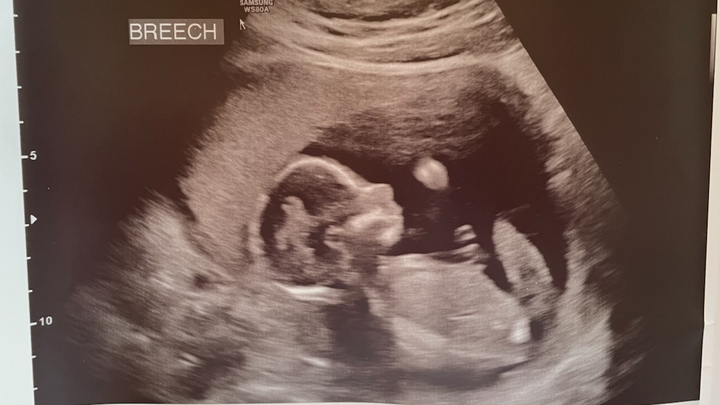

With just separating from the service my only medical coverage is with the VA and as many know that isn't the quickest source to get medical attention. After about two months of waiting we finally were able to go in for our very first ultrasound. What an amazing experience to see little tiny arms moving around and to hear a heartbeat. Everything looked great and we went on to schedule our next appointments. After about another two weeks we received a phone call for the bloodwork and our doctor recommended we came in to discuss. I wasn't sure if this was a routine thing or if it should raise a red flag but I can tell you, we were nervous. After our initial appointment we were referred the same day for a follow on appointment with a Fetal Maternal Clinic where they deal with high-risk pregnancies.

At this point we were unsure what we would be told at this doctor but more testing was done and we came to the conclusion that our little girl has a chance of having Trisomy 18. For those not sure what that means, it is a mutation in the cells that causes severe developmental issues. With that being said, our ultrasounds over the weeks began to illustrate all of the things you read on the internet which began to break our hearts. The development of Ellie's brain, facial structure, and ankles has confirmed among other tests that she does have this condition.

En este punto no estábamos seguros de lo que nos dirían en este médico, pero se hicieron más pruebas y llegamos a la conclusión de que nuestra niña tiene posibilidades de tener trisomía 18. Para aquellos que no están seguros de lo que eso significa, es una mutación en las células que causan graves problemas de desarrollo. Dicho esto, nuestros ultrasonidos a lo largo de las semanas comenzaron a ilustrar todas las cosas que leías en Internet que comenzaron a romper nuestros corazones. El desarrollo del cerebro, la estructura facial y los tobillos de Ellie ha confirmado, entre otras pruebas, que padece esta afección.